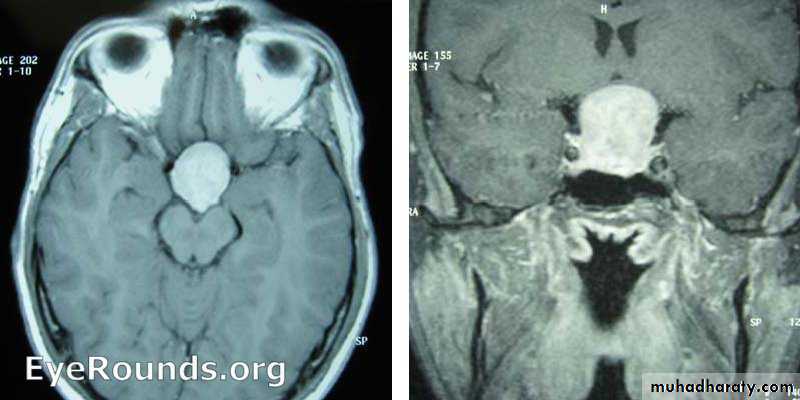

OLFACTORY GROOVE MENINGIOMA MRI’S

PITIUTARY TUMOR AXIAL & CORONAL MRI’S